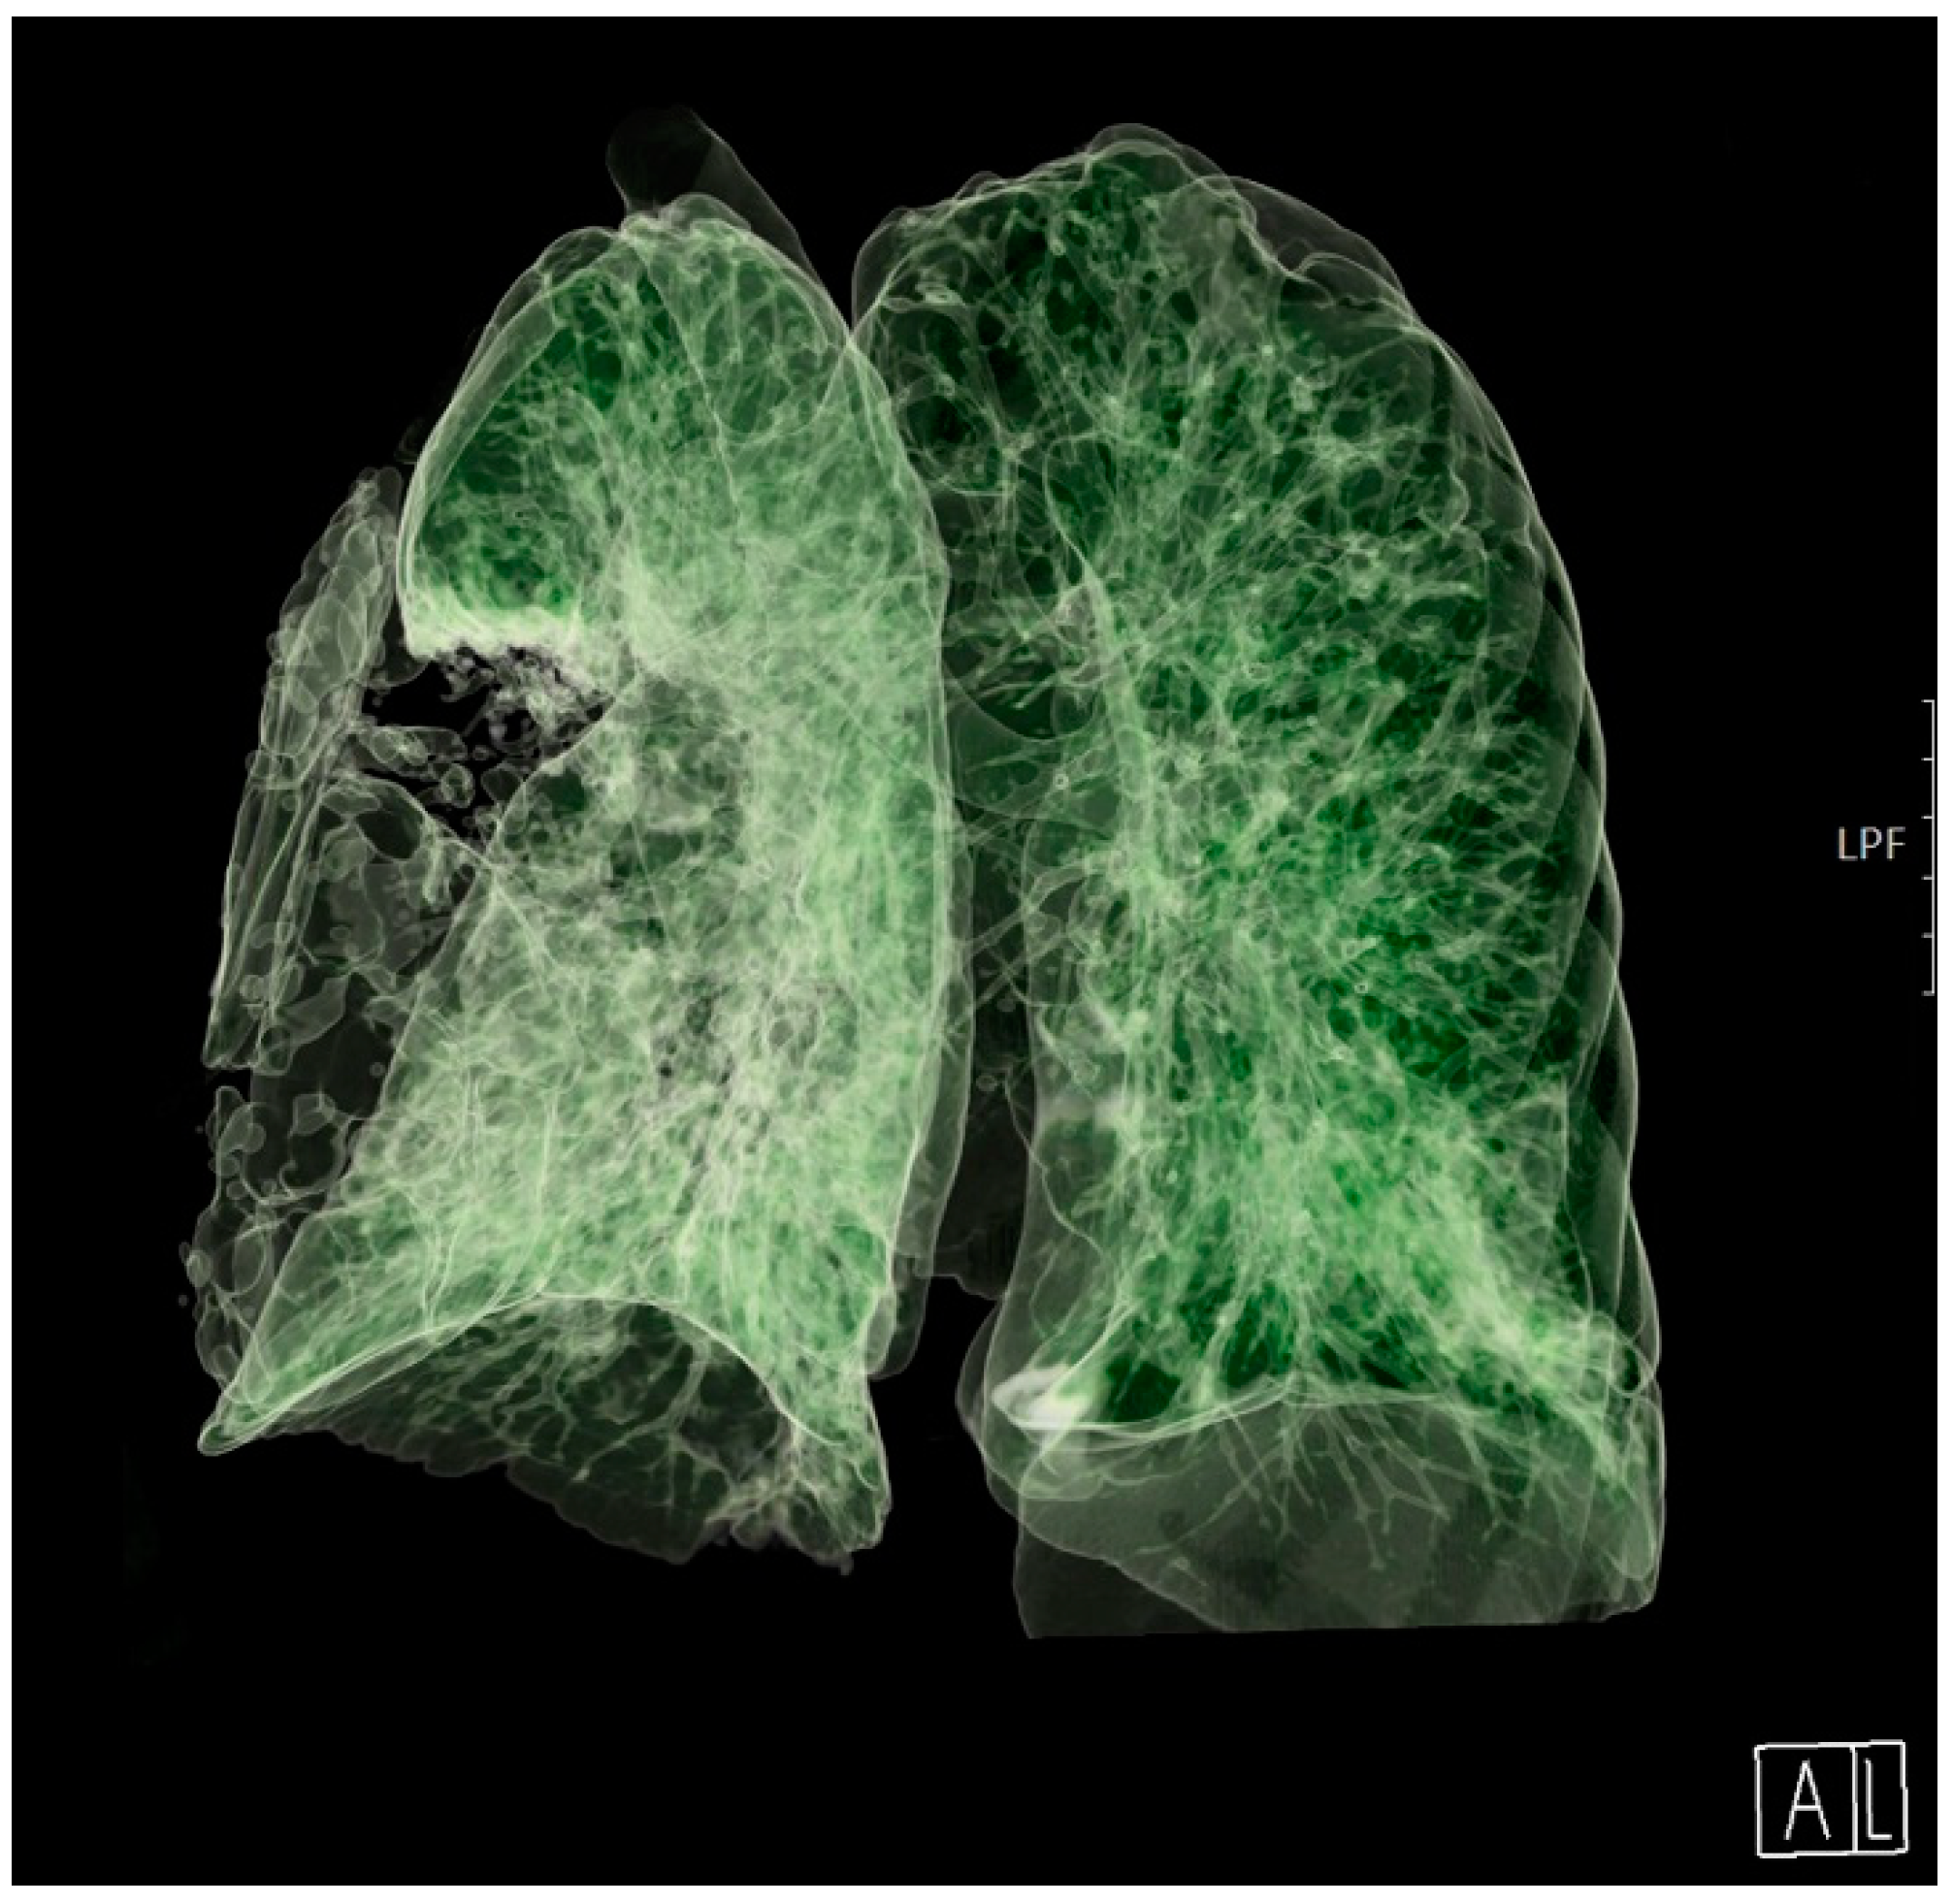

The patient’s clinical condition improved in the following days, and he continued to breathe spontaneously with oxygenation. The control chest radiograph of the lung revealed complete expansion of the lung parenchyma with lung infiltrates on the medial and lower lung lobes. The patient’s general condition gradually improved, and he was transferred to the ward on day 19 after ICU admission with supplemental oxygenation of 4 L O2/min via the nasal catheter and frequency of 18–20 breaths/minute with adequate oxygen saturation of 95–97%. The thoracic drain was removed on the ward (Figure 3).

Figure 3. A 3D computed tomography scan of the lungs 25 days after admission to the Intensive Care Unit. A: anterior, L: lateral.